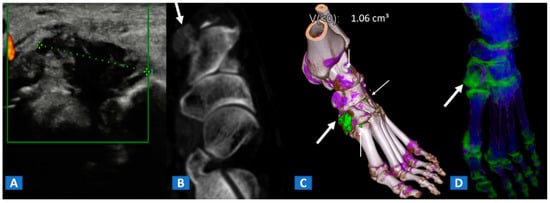

BME represents a common imaging change that is detectable in several inflammatory disorders of the skeletal system, such as autoimmune or septic arthritis. While BME can be used to evaluate the response to therapy in the short term, bone erosions and morphological changes can be used to evaluate the course of disease in the long term (Figure 8 and Figure 9). In cases of advanced inflammatory arthritis, the presence of osteopenia makes it easier for DECT to identify BME, while high resolution CT images can finely identify bone erosions, articular space narrowing and bone remodeling (Figure 8). In painful gout, in addition to identifying tophi, DECT can also assess bone remodeling and detect associated BME [14] (Figure 9). Furthermore, DECT can accurately evaluate BME in patients with sacroiliitis associated with axial spondylarthritis [13].

Figure 9.

A 48-year-old female with painful gout. Upon ultrasound study, a hypoechoic tophus is identifiable (A). In the axial CT image with soft-tissue window (B), the tophus shows soft-tissue density (arrow). On the 3D DECT image for gout analysis (C), the tophus is coded in green (thick arrow). Note the presence of tiny additional tophi (thin arrows). On the DECT 3D map (D), BME can be identified on the intermediate cuneiform and on the base of the first metatarsal bone; this may be an additional factor contributing to pain.